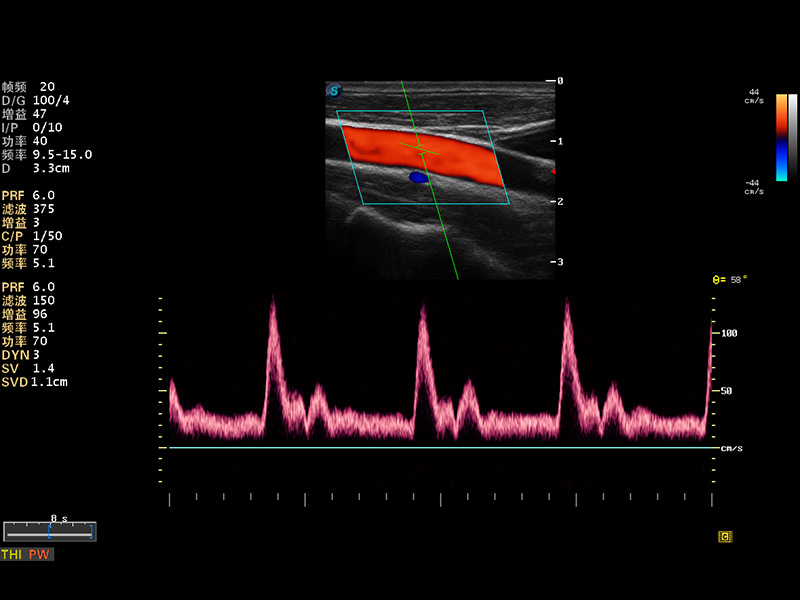

S8 EXP便携式彩色多普勒超声诊断仪是狗万官方网站研发的高端全身应用型便携彩超。高通道的VIS平台融合可视化(Visual)、智能化(Intelligent)和人性化(Smart)的特点,配以狗万官方网站自主研发生产的探头大家族,使您能够快速、准确的获得病人信息,提高工作效率的同时减轻疲劳。

谐波成像